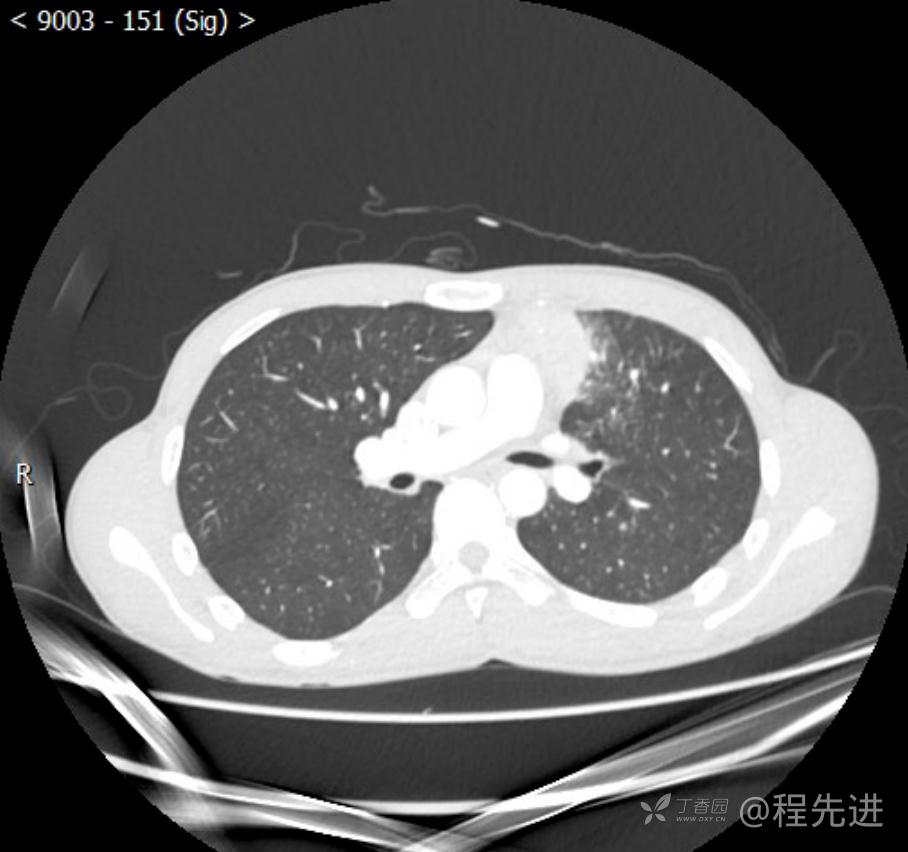

主诉:反复咳嗽1月,发现“纵隔”占位半月,乏力10余天。

现病史:患者1月前无明显诱因出现咳嗽,以夜间为著,伴有少量白痰,无发热,无胸痛、咯血,无痰中带血,未予重视,半月前外院行胸部CT检查发现“左前上纵隔”占位,未予进一步检查及治疗。近10余天自觉乏力,逐渐加重。